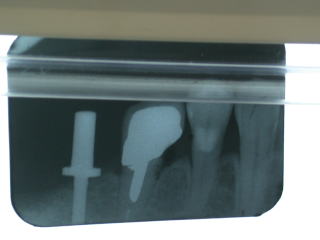

ガム模型上でカスタムアバットメント作製。

インプラントにカスタムアバットメント装着。

手前は通常通りメタルコア装着。